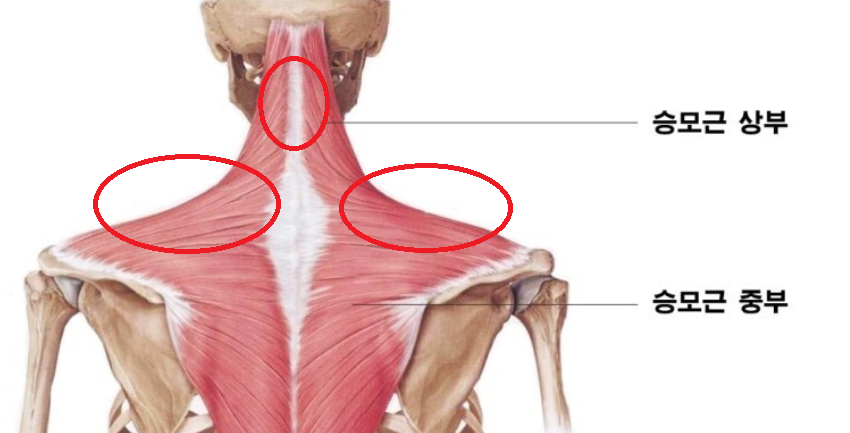

그 과정에서 목의 자세 때문에 목 뒤쪽부터 승모근까지 통증을 자주 느끼고는 합니다.

결국 머리가 앞으로 치중하다보니, 머리의 무게중심이 앞으로가고

머리를 받치고 있는 아래 승모근이 더 큰 힘을 받게 된다고 합니다.

이러한 자세가 지속하다 되면 승모근 쪽의 통증이 유발되게 되고